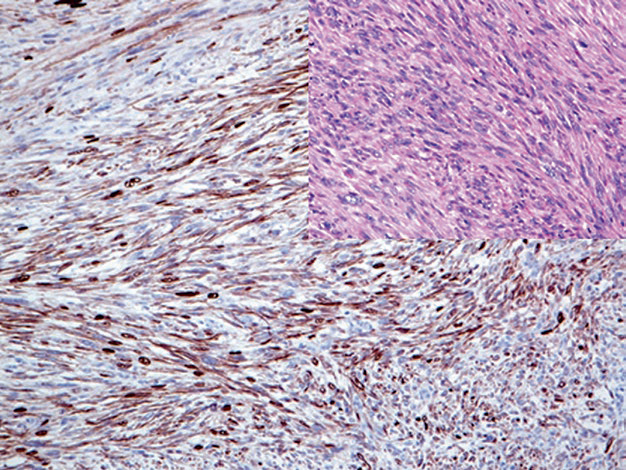

Figure 3. In embryonal rhabdomyosarcoma, EGFR shows strong positive expression.